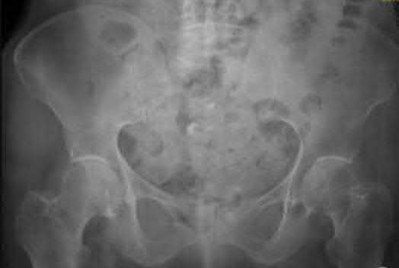

A 35-year-old male sustains an APC-III pelvic ring injury following a high-speed motorcycle collision. After initial hemodynamic stabilization, the surgeon elects to perform an open reduction and internal fixation of a widened sacroiliac (SI) joint via an anterior approach. During dissection and plate placement over the sacral ala, which neurological structure is at greatest risk of iatrogenic injury?

Explanation

During the anterior approach to the sacroiliac joint, the L5 nerve root is at significant risk. It courses directly over the sacral ala, typically approximately 2 cm medial to the SI joint, before joining the sacral plexus. Retraction or misplaced drills/screws in this region can easily injure the L5 root, leading to foot drop and sensory deficits.